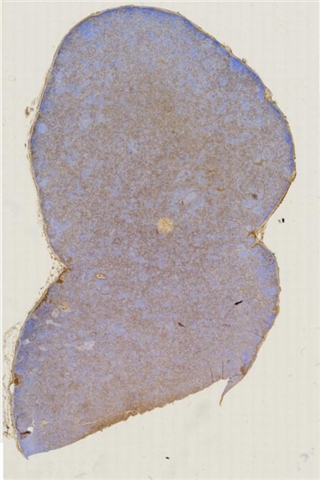

案例3 (6862)

性别:       年龄:65

患者详情: 患者3月余前在当地社区卫生服务中心体检发现血肌酐升高(109.8umo/L),无明显尿量减少,无颜面下肢浮肿无腰酸腰痛,无肉眼血尿,无关节疼痛,无皮疹红斑,开始未重枧及进一步诊治。10余天前患者到中山医院复查生化提示“肌酐200umol/L、尿素7.3mmol/L、尿酸637umol/L、白蛋白34g/L、球蛋白66g/L、蛋白电泳β15.0%、蛋白电泳Y42.6%”,同时其它检查提示“血lgG4 54.20g/L”。 CT:纵隔及双侧腋下多发肿大淋巴结,肺动脉干稍増粗,主动脉硬化,扫及双肾饱满,后腹膜发淋巴结。 PET-T:全身多区域淋巴结肿大、双侧泪腺、双侧颌下腺及胰腺体尾部饱满、双肾实质肿胀,左侧头皮局部增厚,伴FDG代谢增高,鼻咽顶后壁及前列腺腺体FDG代谢增高,上述病灶首先考虑IgG4相关性疾病所致可能,建议暖股沟淋巴结活检病理明确除外淋巴瘤。

大体所见: 结节一枚3*3*2cmA-C。

医院: 上海交通大学医学院附属仁济医院